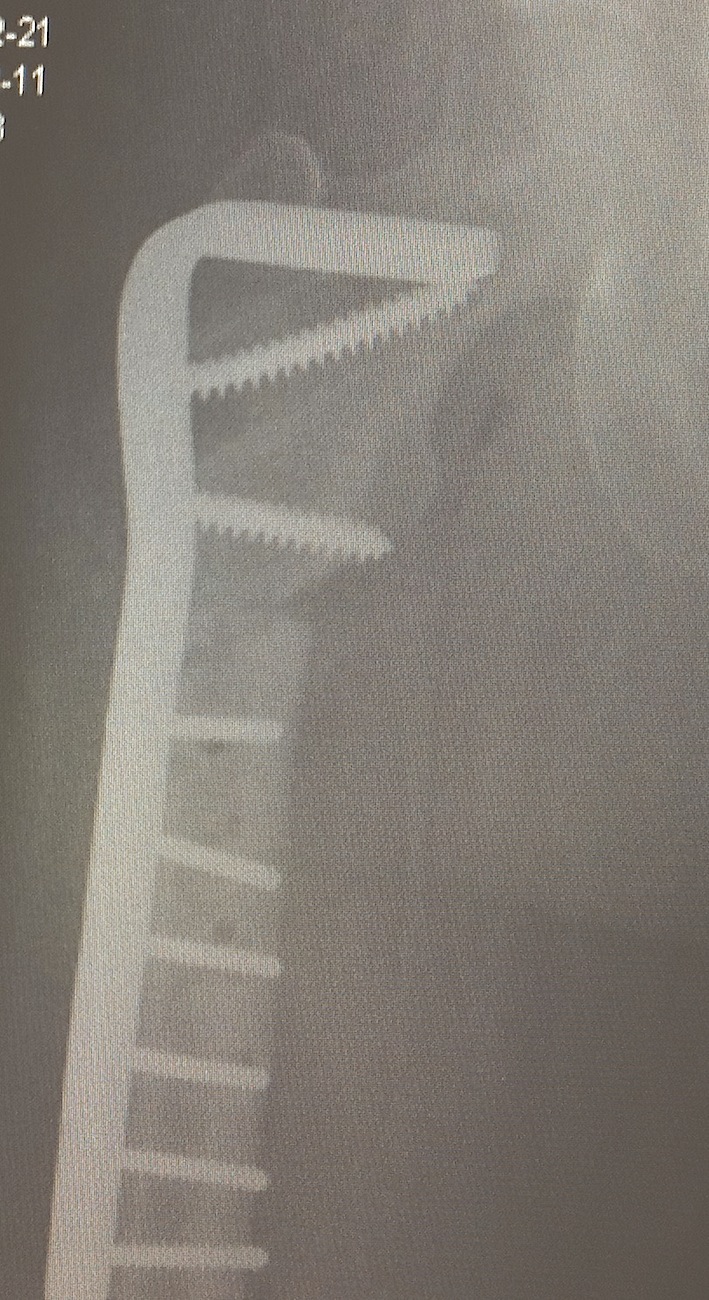

B. Cephalomedullary nails

- gold standard

- load sharing or load bearing, dependant on reduction

Piriformis reconstruction Gamma nail TFNA with helical screw Intertan nail